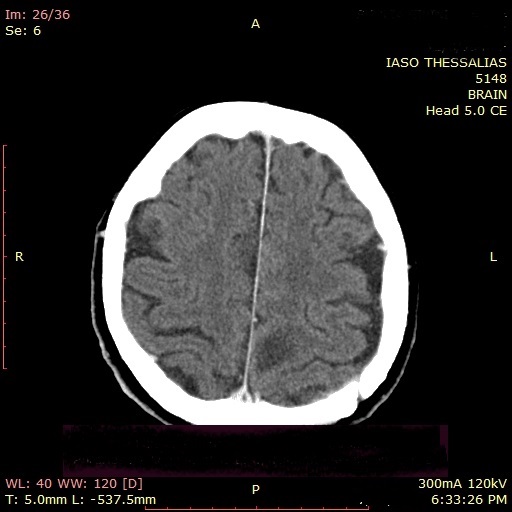

Στο ΙΑΣΩ Θεσσαλίας, στο Τμήμα Εκτάκτων Περιστατικών, προσήλθε ασθενής, 80 ετών, λόγω διαταραχής βάδισης και μείωσης επιπέδου συνείδησης. Οδηγήθηκε στην Α΄ Νευροχειρουργική Κλινική, Διευθυντής της οποίας είναι ο Δρ Βασίλειος Σλατινόπουλος, κι εκτιμήθηκε από τη Νευρολόγο, κυρία Κλαίρη Χαρισίου. Αμέσως, κρίθηκε απαραίτητη η διενέργεια αξονικής τομογραφίας εγκεφάλου στο Τμήμα Ιατρικών Απεικονίσεων, η οποία ανέδειξε εξεργασία (μηνιγγίωμα παραοβελιαίο) αριστερού εγκεφαλικού ημισφαιρίου.

Απεικονιστικά, η πρώτη εξέταση που συνήθως ανευρίσκεται ένα μηνιγγίωμα είναι η αξονική τομογραφία εγκεφάλου, ενώ η εξέταση εκλογής είναι η μαγνητική τομογραφία με χορήγηση παραμαγνητικής ουσίας. Επιπλέον, η μαγνητική φασματοσκοπία πρωτονίου (MRS) δίνει στον Νευροχειρουργό πληροφορίες για τα μεταβολικά χαρακτηριστικά του μηνιγγιώματος.